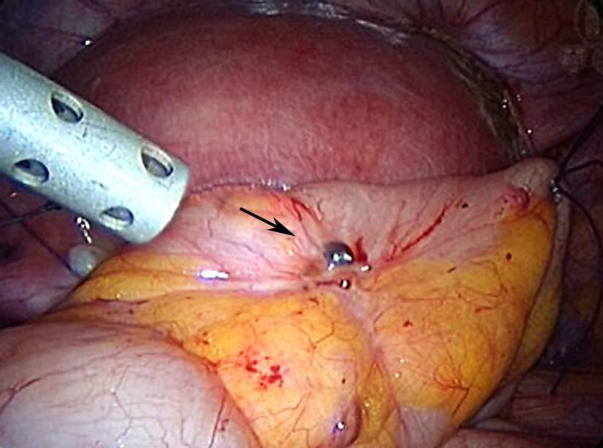

宫骶韧带、子宫直肠陷凹子宫内膜异位症